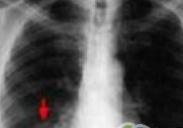

小兒支氣管肺發育不全

• 小兒支氣管肺發育不全

628健康網為您分享有關小兒支氣管肺發育不全的癥狀,小兒支氣管肺發育不全的治療方法,小兒支氣管肺發育不全的預防知識...